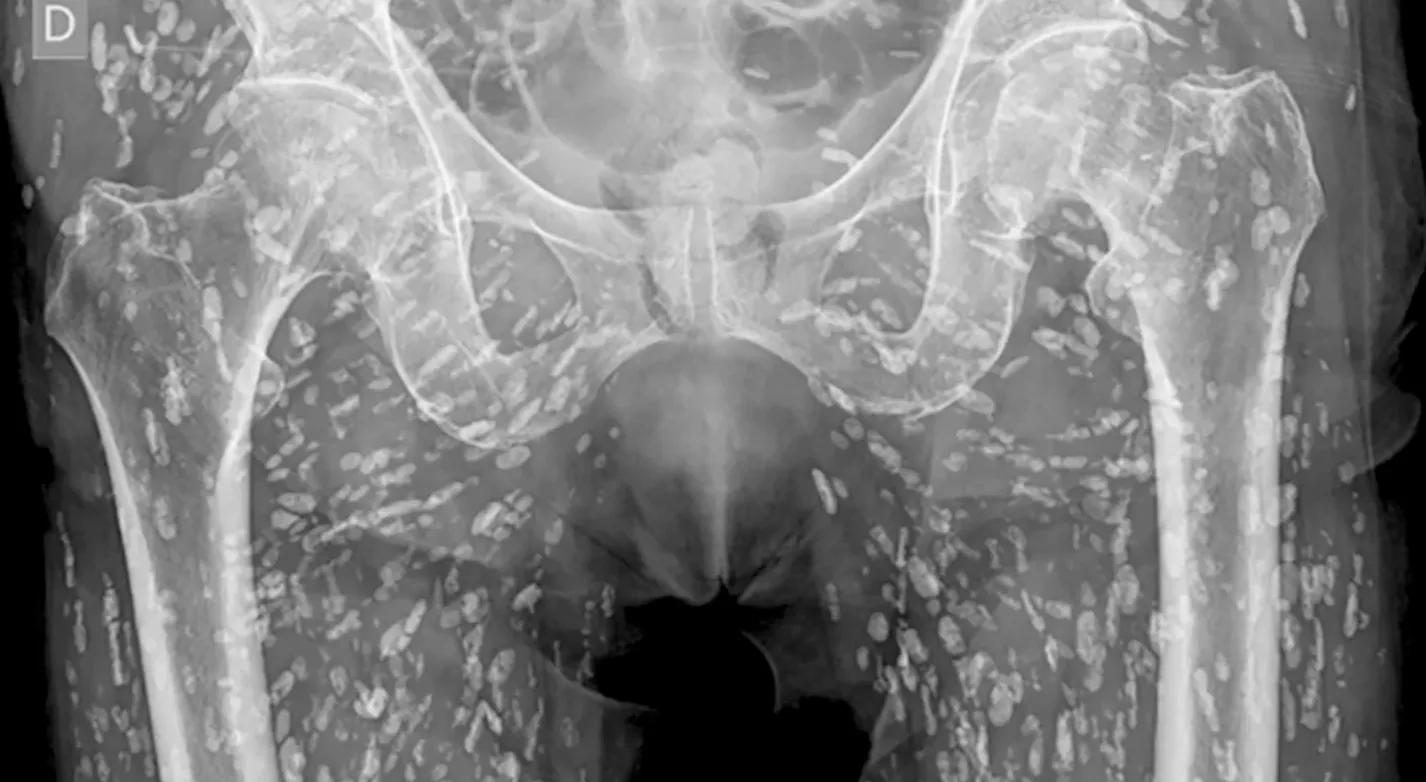

Horrifying X-ray shows tapeworms breeding inside man’s body after he made vital kitchen error

‘This is one of the most insane X-rays I’ve ever seen’

A doctor has shared stomach-turning X-ray images of a man who had tapeworms breeding inside of him after he made a serious kitchen error.

Sam Ghali, an Assistant Professor in Emergency Medicine at the University of Florida, shared the shocking images in a post on X, saying it was “one of the most insane X-Rays I’ve ever seen.”

Speaking over the X-Ray pictures, Dr Ghali explained that the small white marks were dozens of calcified tapeworm eggs, which had been laid in the soft tissue of the man’s pelvis.

The parasitic worms had made their way into the man’s body after he at undercooked pork, a condition is known as cysticercosis.

This is where larval cyst of taenia solium make their way into the body. Once there, they can burrow into muscular and soft tissue and travel “throughout the entire body,” Dr Ghali said.

He explained: “These cysts can travel anywhere throughout the entire body, heavily to the muscular and soft tissue of the hips and the legs. This condition comes from when the patient eats undercooked, or raw, pig. If just in the pelvis, they don’t pose a life-threatening problem. The problem is if they travel to the brain and lodge there.

“That can cause very serious issues. As you can imagine, that can lead to neurological symptoms like headaches, confusion, seizures and even death. The moral of the story is never eat raw pork.”